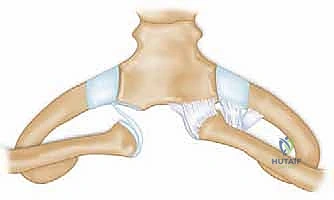

Modern stabilization relies on robust biological reconstruction. While primary repair of the capsule using suture anchors in the manubrium can augment the construct, a figure-of-eight graft reconstruction is the gold standard for restoring multiplanar stability. A semitendinosus or gracilis autograft (or allograft to minimize donor site morbidity) is preferred due to its length and tensile strength.

Drill holes, typically 4.0mm to 4.5mm in diameter, are meticulously created. In the medial clavicle, two holes are drilled from anterior to posterior, approximately 1 cm lateral to the articular margin and 1 cm apart. In the manubrium, two corresponding holes are drilled. Critical Step: When drilling the manubrium and the clavicle, a malleable retractor or a broad periosteal elevator must be placed deep to the bone to protect the mediastinal structures from the drill bit plunging. The drill must always be directed from anterior to posterior, with precise control.

The graft is then passed in a figure-of-eight configuration. Suture passing wires or curved shuttles are used to navigate the graft through the osseous tunnels. The graft is tensioned with the clavicle held in anatomical reduction (often requiring downward and posterior pressure on the medial clavicle). The graft limbs are then sutured to themselves and to the surrounding periosteal tissues using heavy, non-absorbable, braided sutures.

Some modern techniques utilize a "docking" method, where the graft is fixed into blind-ended sockets using biocomposite tenodesis screws, minimizing the need for posterior dissection and reducing the risk to mediastinal structures. Regardless of the specific graft routing, the final construct must be rigidly stable through a functional range of motion on the operating table.